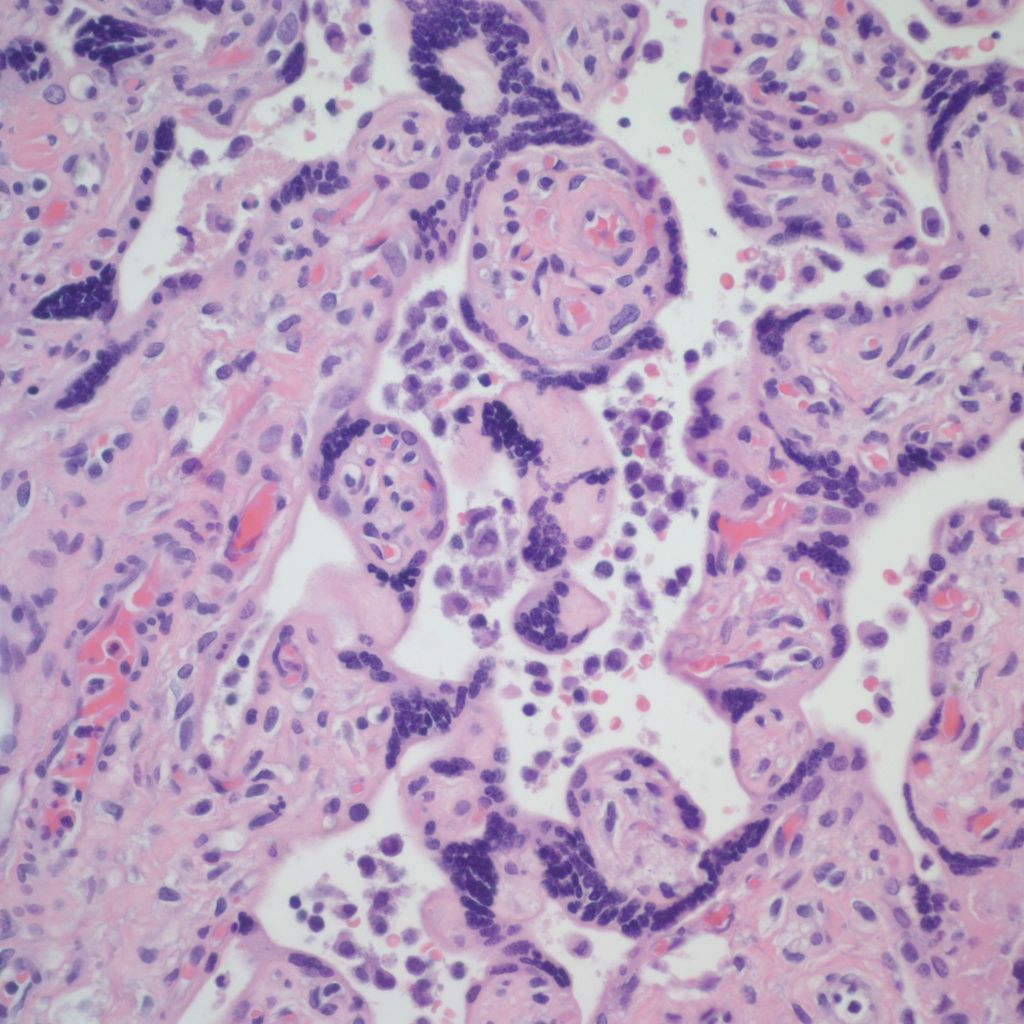

There is a focus of intervillous fibrinoid with no definite cytotrophoblast that is not re-covered with syncytium suggestive of recent syncytial injury (F). (10x, H&E)

CHIV with prominent perivillous fibrinoid deposition